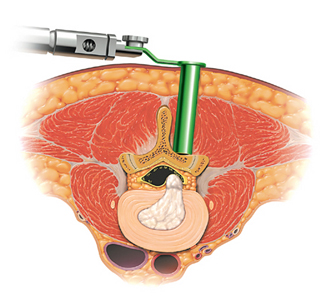

The surgery is performed through a small skin incision on the back.   A narrow tube is gently inserted through the soft tissue under fluoroscopy (x-rays) with the aid of a minimally invasive muscle retracting system. This retractor helps minimize damage to the muscles and soft tissue. With the aid of a high-powered microscope, the herniated disc can be removed with specially-designed microsurgical instruments to relieve pressure from the nerve root. The skin is closed using dissolvable sutures and sterile superglue. Some patient’s may require a back brace after surgery.

Minimally Invasive Microdiskectomy Illustration